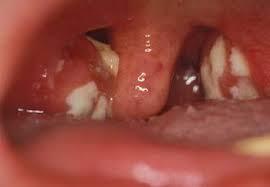

При непосредственном осмотре области миндалин визуализируется пленка беловато-желтовато-серого цвета. По внешнему виду она напоминает пятно от стеариновой свечки округлой формы. Пленка мягкая (по консистенции), окружена воспалительным (красным, отечным) ободком по краю и легко снимается ватным тампоном, после чего на его месте остается изъязвленная поверхность желтоватого цвета с ровными четкими контурами, которая кровоточит.

На первых порах заболевания язвенная ангина поверхностная. Но в случае длительного течения заболевания, дефект в тканях становится глубоким, приобретает кратерообразную форму, распространяется за пределы миндалины, вовлекая глубокие ткани. Иногда в патологический процесс вовлекается слизистая оболочка десен, язык и даже надкостница.

Для пораженной миндалины характерно увеличение в размерах. Она покрывается серовато — желтым налетом с дурным запахом. Его легко можно убрать медицинским шпателем. Симптомы гнойно воспалительного поражения проходят за 2 недели.

При наличии симптомов некротической ангины следует обязательно обратиться к врачу. В процессе обследования доктор может обнаружить на миндалинах:

- серый или желтый налет;

- язвы с неровными краями.